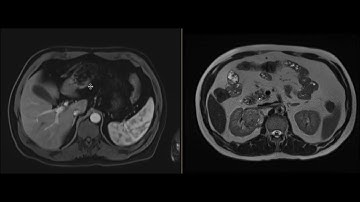

Duodenal GIST